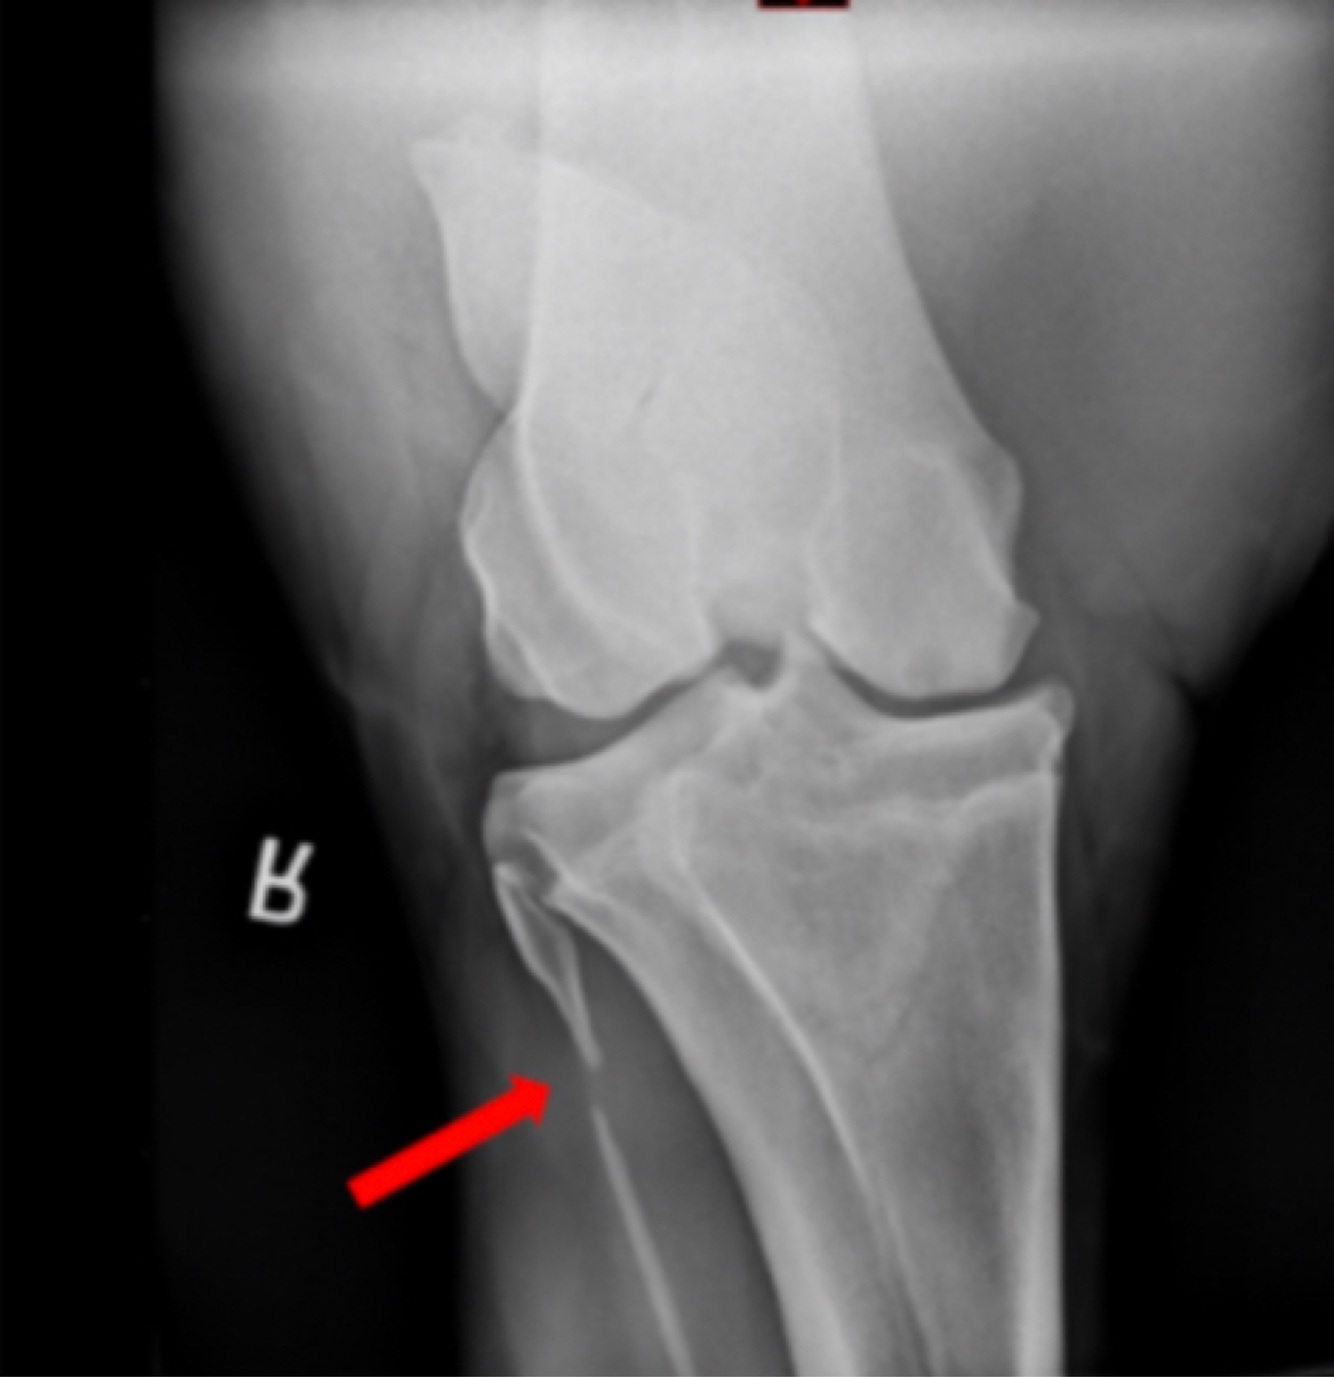

13

Q

Interpret the finding indicated by the arrow

A. Fracture

B. Incomplete ossification of the fibula

C. Bony lysis indicative of infection

A

B.